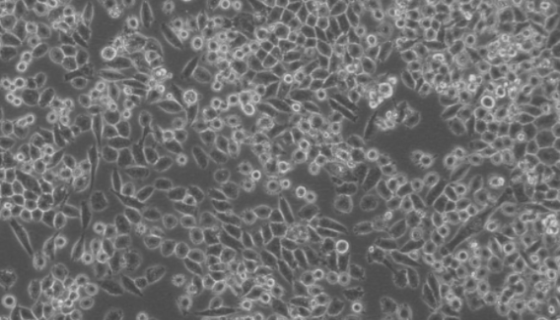

JF305人胰腺癌细胞来源于人胰腺,呈上皮细胞样,贴壁生长。